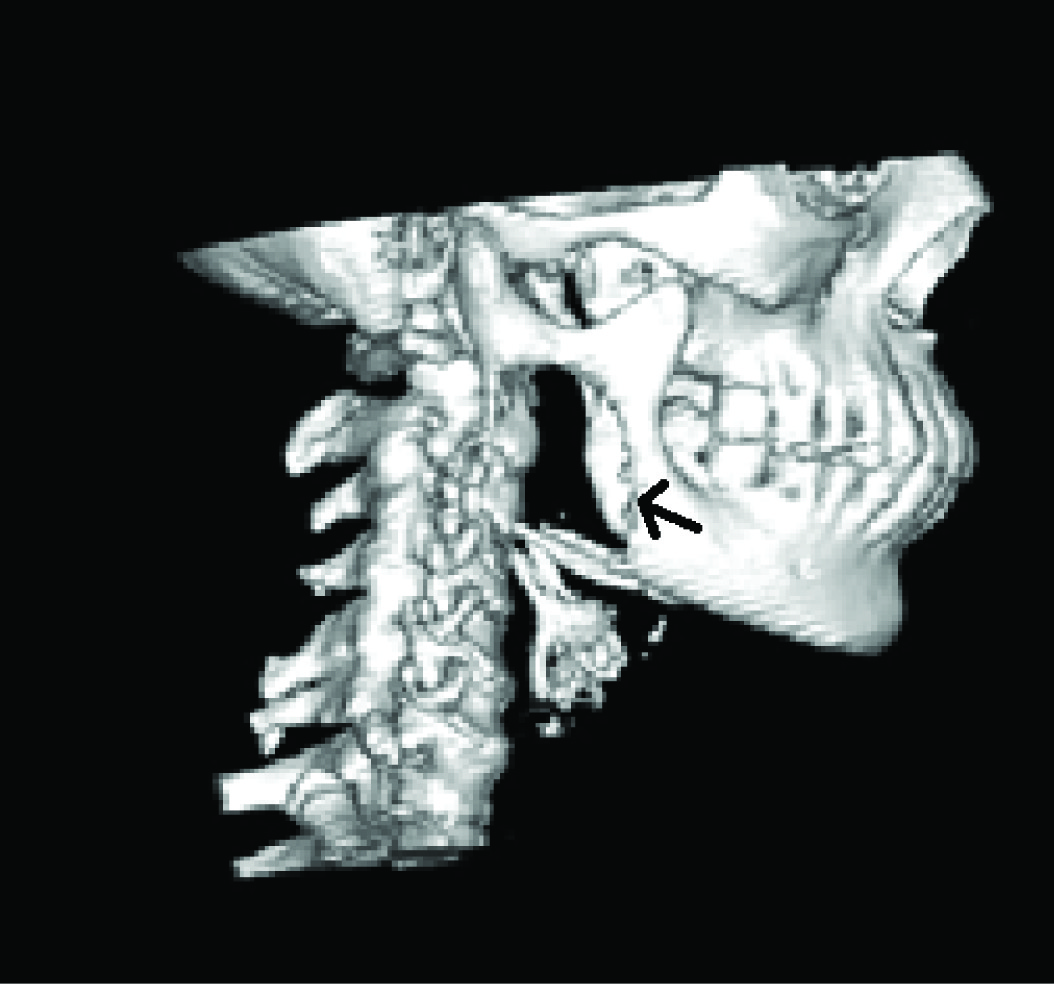

CT scan [Table/Fig-3] revealed an osteolytic lesion with predominantly soft tissue mass measuring 6.2 cm X 4.0 cm on the right ramus of the mandible. 3–D CT [Table/Fig-4] confirmed the OPG findings and depicted a pronounced destruction of bone at the angle and posterior border, with destruction of medial and lateral cortices. This Sectionmade us clinically diagnose a fast growing solid tumour in the ramus. The clinical differential diagnosis included odontogenic tumours, neural sheath tumour and secondary metastasis from elsewhere.

3 D CT showing the lesion